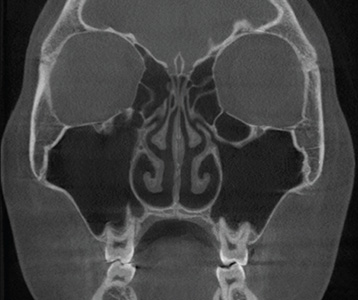

• 재수술 전

• 재수술 후